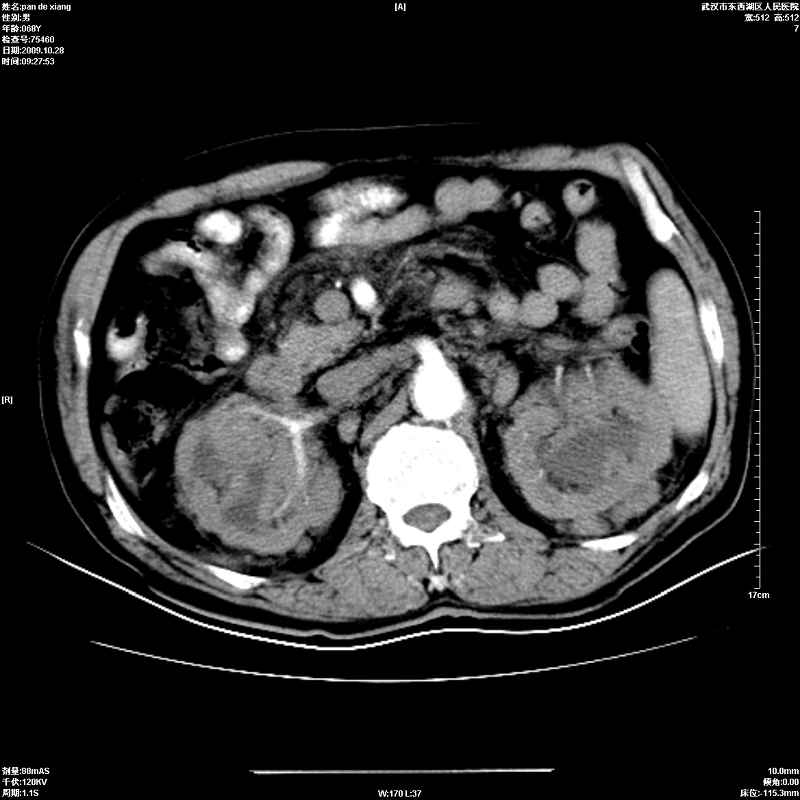

以下是引用杀毒软件在2009-10-28 20:41:00的发言:[br]结合临床考虑---白血病双肾改变或淋巴瘤。

以下是引用zxl51642在2009-10-29 9:59:00的发言:[br]结合临床“单克隆免疫球蛋白血症”,考虑双肾为继发损害并肾功能不全(尿中大量igg及少量iga、igm等大分子免疫球蛋白滤出所致继发损害),椎前软组织肿块为髓外造血。与浆细胞瘤有区别,平扫时有战友说的很清楚。